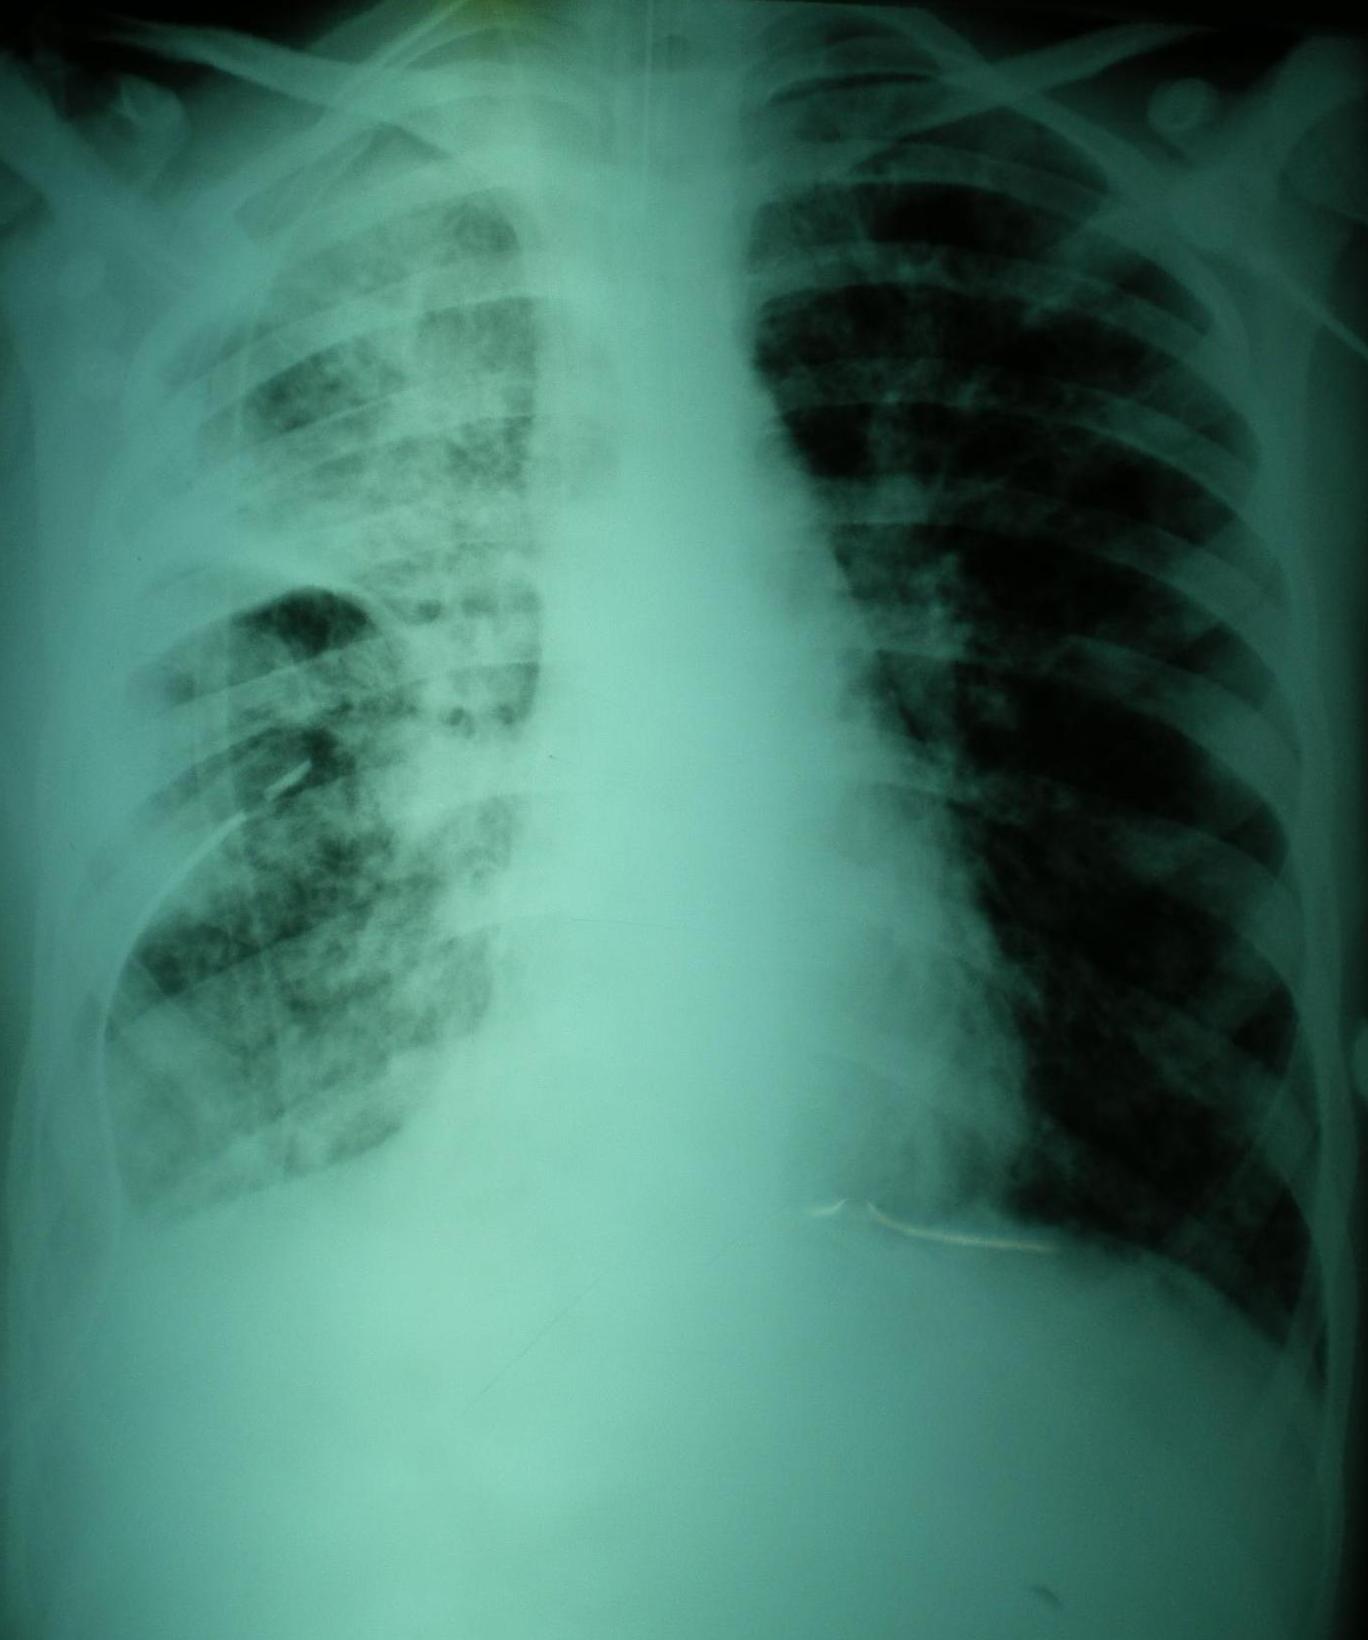

El edema pulmonar post-reexpansión puede producirse luego del tratamiento de grandes derrames pleurales, neumotórax o de atelectasias obstructivas. Se relaciona a la acción de mediadores inflamatorios que aumentan la permeabilidad vascular con exudación a los alvéolos. Comienza inmeditamente despues de la reexpansión y cede a los 5 a 7 dias; puede unilateral, bilateral o limitado a un único lóbulo. Los factores de riesgo son edad < 40 años, larga duración del colapso pulmonar (> 4 días), derrames pleurales > 1500 cc, neumotórax grado 3, rápida reexpansión, y aplicación de presión negativa intrapleural. El tratamiento es de soporte, pero lo mas importante es la prevención reconociendo los factores de riesgo para su desarrollo ya que tiene una mortalidad superior al 20%.